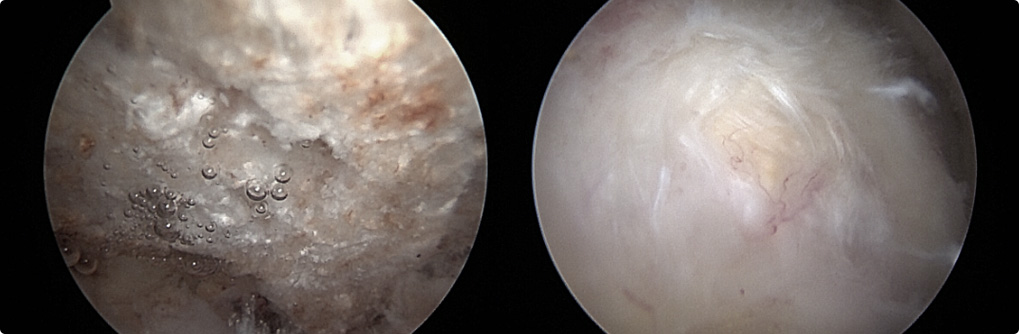

관절 내시경을 통한

견봉 성형술

관절 내시경을 통하여

힘줄 손상을 유발하는 견봉하 골극을 제거합니다.

이러한 경우

내시경 시술을

고려합니다.